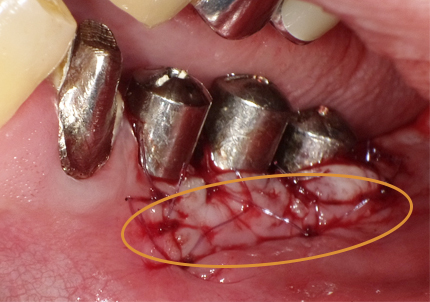

15.角化歯肉の獲得の為に歯肉弁根尖側移動術(2019年8月)

➡歯肉弁根尖側移動術とは・・・歯やインプラントの周りを磨きやすくし、長持ちさせるため、歯ぐきを下の方向(歯の根の方)へ動かして固定し、安定した歯ぐきを増やす手術

① 炭酸ガスレーザーにてインプラントヘッド部のパンチアウト

② 骨頂部の歯肉を骨膜を残して剥がし、反転する

16.歯肉弁を根尖側に移動し縫合を行ったのち、歯周パックにて創面の保護

6.二次手術

インプラント周囲の角化歯肉(付着歯肉:骨に固定されてる歯肉)の獲得を目的に歯肉弁を移動する